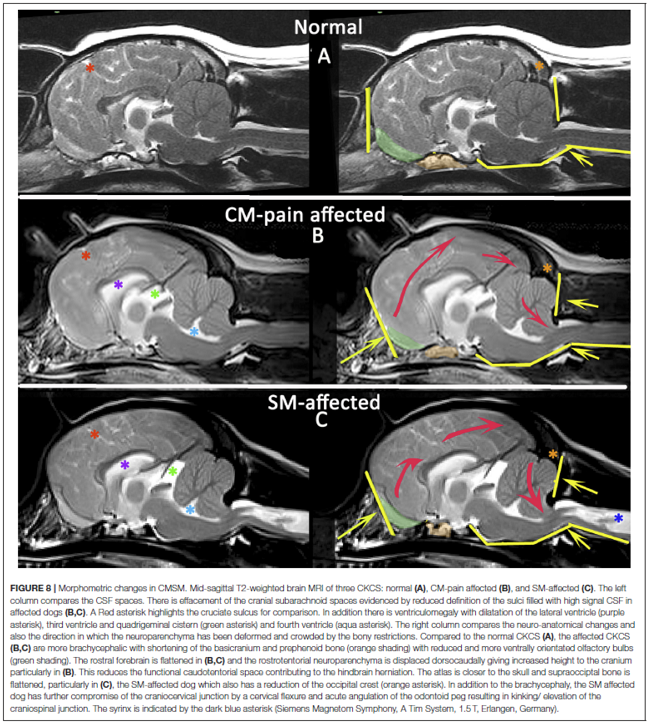

In a November 2019 article, a team of UK researchers reviewed the medical records of 66 cavaliers, 40 of which had syringomyelia (SM) and the other 26 did not; 55 had Chiari-like malformation (CM) and 11 did not. The dogs were grouped by (1) control group of 11 with no Chiari-like malformation (CM-N); (2) CM pain group (CM-P) of 15 dogs; (3) clinical SM group (SM-S) of 40 dogs. SM-S dogs included those with outward symptoms of SM (variable phantom scratching, scoliosis, etc.) and a syrinx of at least 4 mm. The researchers divided their study into two sub-sets, the first examined head features related to the dogs' soft palates, and the other examined features related to their hard palates; both sub-sets also included review of the dogs' features related to forebrain flattening and olfactory bulb rotation. The olfactory bulb is a bulb of neural tissue within the dog's fore-brain. Their work included comparing the shape of the "stop" of each dog, which is the degree of the angle where the nose and skull meet, and the indentation between the eyes at that point. A "gentle stop" has the least angular shape and a "pronounced stop" has the sharpest angle.

They found (see figure 5 below):

• CM-N dogs (no CM) had the least brachycephalic head, a gentle stop with the greatest upper jaw area between the hard palate and the frontal bone, and the longest soft palate length.

• CM-P dogs (painful CM) had the least distance between the hard palate and cranium, a pronounced stop, and a displaced olfactory bulb.

• CM-S dogs (large syrinx) had the most reduced middle craial bone area and shortest distance between the connection of the hard and soft palates with the base of the cranium.

They conclude that dogs with CM-P had the shortest muzzle lengths, and that "a reduced distance between the hard palate and the frontal bone was particularly associated with CM-P." Dr. Clare Rusbridge, one of the researchers, explained:

"Dogs with clinically relevant CM/SM are more likely to have brachycephalic features of the rostral skull flattening with reduction of nasal tissue and a well-defined stop. This evidence not only enhances our understanding of the disease and 'at risk' head conformation but could also impact on the assessment of MRI and disease diagnosis. It suggests the whole skull should be analyzed and not just the hindbrain currently required in prebreeding screening. This information has implications not only for breeders and pet owners but also for the veterinary profession to raise awareness about the welfare aspects of breeding. Furthermore, an increased risk for SM and painful CM might not be confined to brachycephalic breeds but other miniaturized purebreeds and hybrids that have gained in popularity as pets."

Co-researcher Dr. Susan P. Knowler explained:

"This study suggests that the whole skull, rather than just the hindbrain, should be analysed in diagnostic tests. It also impacts on how we should interpret MRI from affected dogs and the choices we make when we breed predisposed dogs and develop breeding recommendations. ... The brachycephalic features that can be seen from outside is a head that has flattening at the front with reduction of nasal tissue and a well-defined stop."